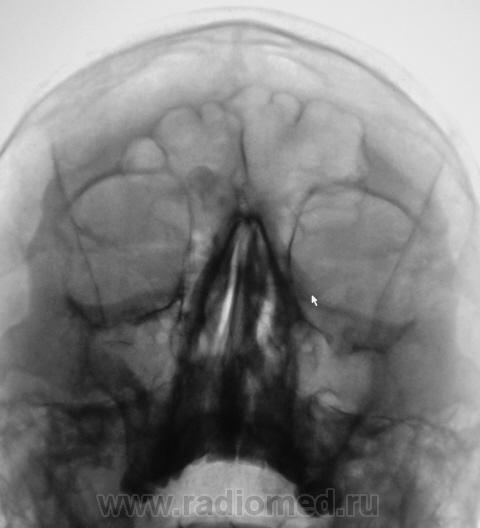

Касательно пристеночного уплотнения справа в в/ч пазухе- вполне возможно суммационное искажение из-за неправильной укладки,с учетом клиники-я бы перестраховался и назначил томограмму(в идеале-малодозовый режим СКТ на ППН). Можно назначить контроль в динамике.

Образование правой лобной пазухи,пристеночное утолщение слизистой пр.гайморовой пазухи. Как всегда может помочь томограмма.

Остеома с типичной локализацией. Неосложненная.

Пациент направлен на цифровую флюорографию придаточных полостей носа.